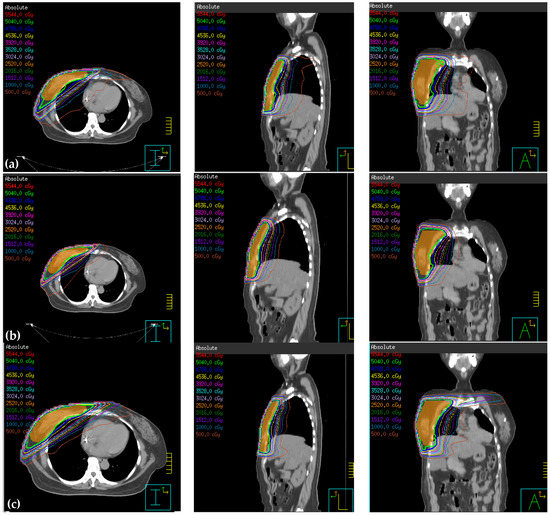

The software used for treatment planning was the Pinnacle3 version 9 RTP. We defined true PTV (tPTV) as the effective PTV margin delineated by the physician after excluding the error region (the part of air and lung). To decrease the surface for achieving greater skin sparing, 0.3 cm retraction of tPTV at the upper border was applied and defined as reduced PTV (rPTV) (see Figure 1). The planning technique extended rPTV to 0.5 cm and added 0.5 cm width in 90% prescription dose constraint circle and 1cm gap as addition area. In all plans, the prescription dose was 50.4 Gy in 28 fractions to the right breast PTV (Table 1). The Elekta Synergy medical linear accelerator was used, the photon energy was 6 MV.

Figure 1.

The green area is the planning target volume (PTV), the red area is the true PTV (tPTV), and yellow area is the reduced PTV (rPTV).

Figure 2.

Treatment planning using (a) intensity-modulated radiotherapy (IMRT), (b) hybrid 3D conformal radiotherapy (3D-CRT)/IMRT, (c) non-continuous partial arc, and (d) continuous partial arc.